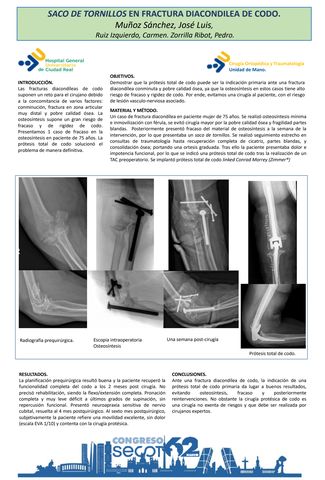

SACO DE TORNILLOS EN FRACTURA DIACONDILEA DE CODO

JOSE LUIS MUÑOZ SANCHEZ, CARMEN RUIZ IZQUIERDO, PEDRO ZORRILLA RIBOT